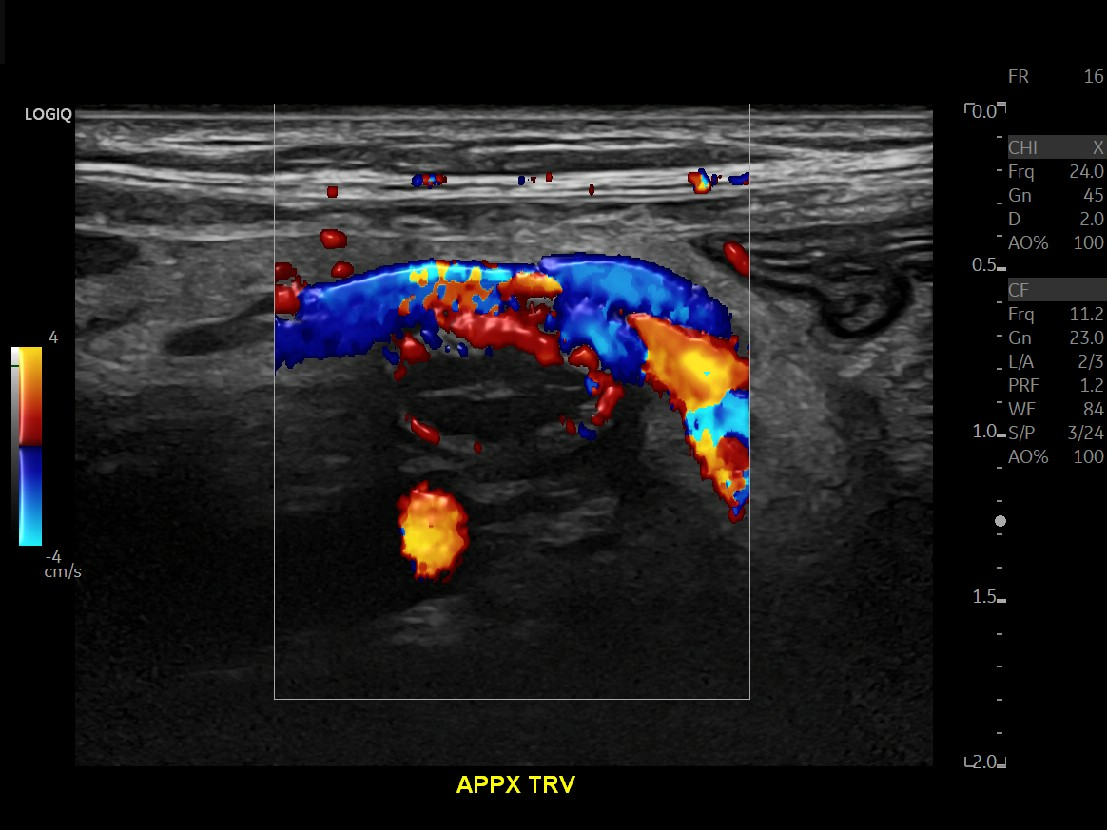

Appendicitis 14

Large appendicitis with appendicolith, hyperemia, fat standing and lympadenitis.